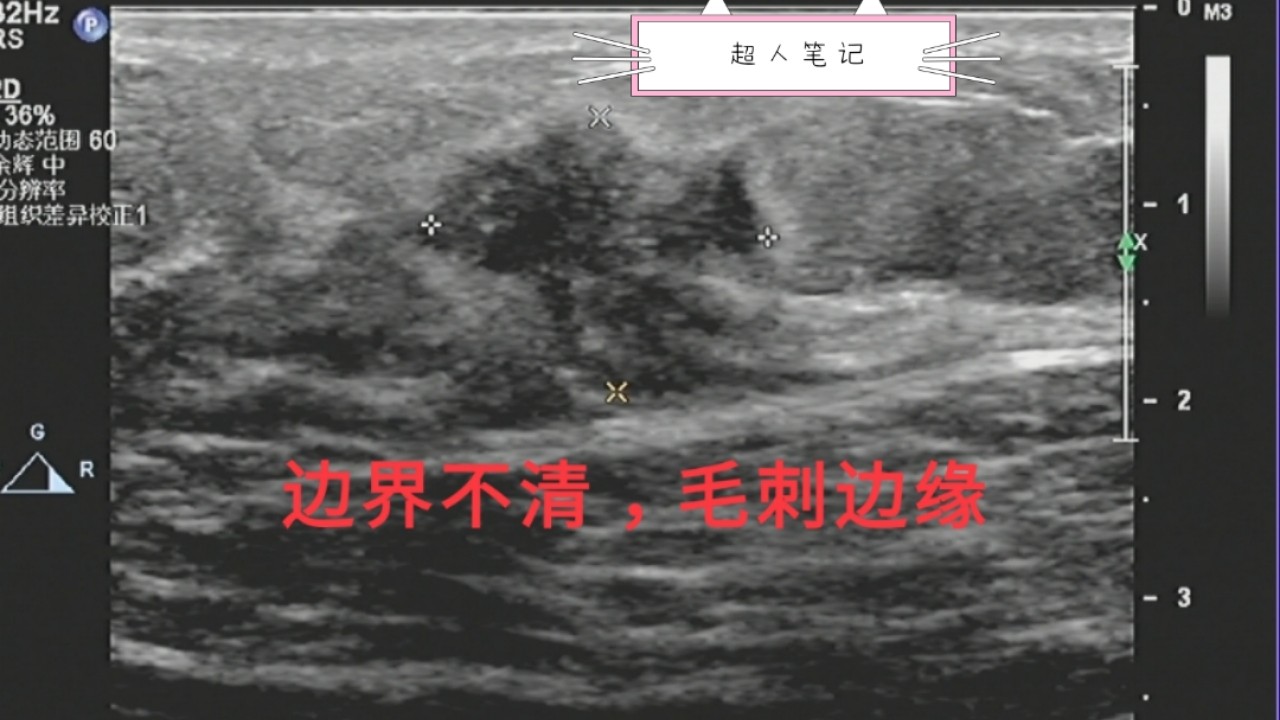

3、边界不清,毛刺状边缘。